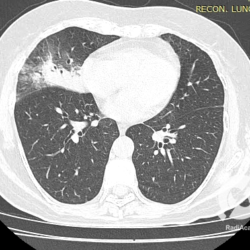

Os agentes etiológicos infecciosos são variados (bactérias, vírus, fungos, parasitas…), mas o que ocorre nos pulmões durante uma infecção por qualquer tipo de agente é a substituição do ar alveolar por secreção (pus, muco, eventualmente sangue ou necrose…) e com isso a manifestação radiográfica vai ser a mesma já que todas estas secreções apresentam a mesma densidade radiográfica: partes moles.

E o nome dado a esta alteração radiográfica que corresponde à substituição do ar alveolar por líquido é a consolidação alveolar.

Uma consolidação alveolar é, por definição, uma opacidade (imagem densa, branquinha) homogênea ou às vezes heterogênea (pela presença de calcificações ou cavidades), de limites mal definidos, exceto quando toca a pleura da parede ou das cissuras pulmonares. É um termo usado tanto em radiografia, como em tomografia computadorizada. Na tomografia, um outro termo é usado: vidro fosco, que é uma opacidade (branquinha mas não tanto como a consolidação), que borra o pulmão mas deixa ver os vasos de permeio (igual bigode de adolescente: dá pra ver todo o fundo).

Nós vamos mostrar aqui um pequeno apanhado de pneumonias de variados agentes, em diversos segmentos e lobos pulmonares, com extensões variadas. O objetivo é identificar o padrão radiológico de consolidação alveolar e não determinar o agente infeccioso, isso vai ser assunto para mais adiante. Aliás já antecipo que é fundamental saber localizar a lesão, porque alguns destes bichos gostam de determinados segmentos, alguns tumores também têm as suas preferências, então localização é fundamental. Se localização não fosse importante, um apartamento na beira do mar sairia o mesmo preço de um apartamento de frente pra BR-101, concordam?